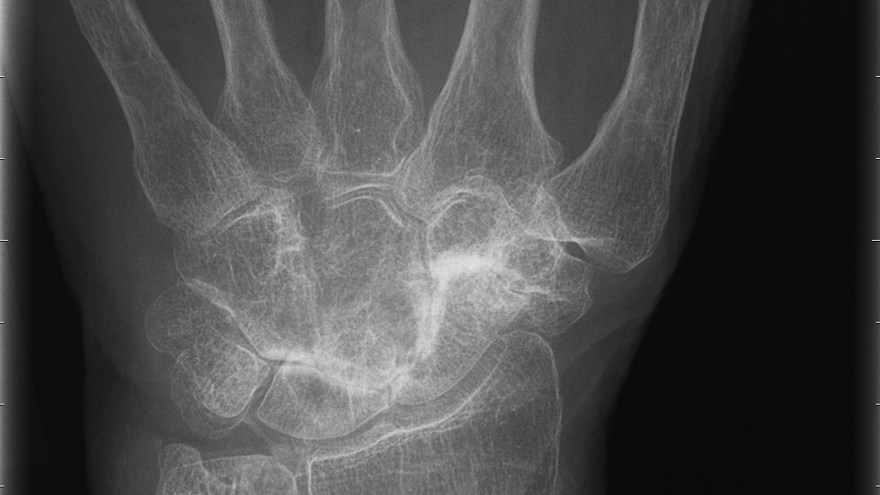

Den vanligaste lokalisationen av primär artros i handen är i tummens carpometacarpalled (CMC 1) – tumbasartros, med eller utan samtidigt engagemang av leden mellan scaphoideum och trapezium (STT-leden).

Tillståndet är 8-10 ggr vanligare hos kvinnor och debuterar vanligen mellan 45-50 år. Kliniskt finner man krepitationer i den engagerade leden samt smärta (”Grinding-test”) vid provokation i form av axial kompression och rotation av tummens bas. Vid engagemang av STT-leden har patienten smärta i handleden vid radialdeviation. Diagnosen fastställs radiologiskt.